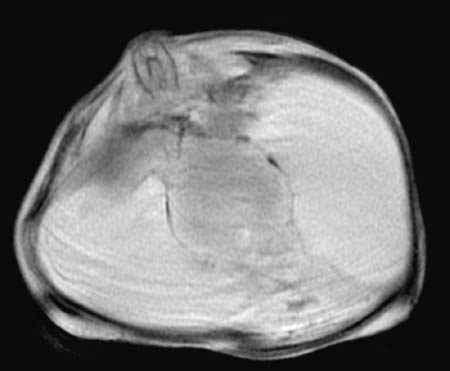

This T1 weighted MRI scan in axial view demonstrates a case of alobar holoprosencephaly with a

proboscis

, which is a poorly formed nose. There is the appearance of central

fused thalami

. Such cases are most typical for trisomy 13.